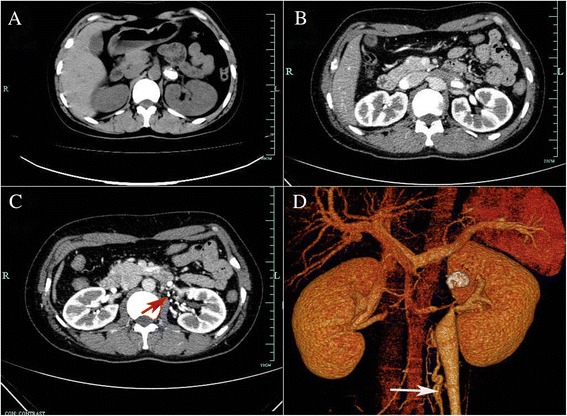

Fig. 3.

The images from the computed tomography (CT). a The noncontrast CT demonstrated left ureter calculus. b The contrast enhanced CT indicated a hyperdense mass in the left renal vein. c The contrast enhanced CT indicated peripheral veins (red arrow) around the left renal hilum. d Three-dimensional CT clearly displayed the calcified RVT with varicose ovary vein (white arrow)

Because the shape of the calculus was unusual and there was no evidence of hydronephrosis, the diagnosis of calculus was questioned. Further evaluation to determine the true nature of the hyperechoic lesion included computed tomography (CT) without contrast, which showed the calculus in the left ureter (Fig. 3a). In addition, intravenous pyelography showed that the pelvic areas around both kidneys were normal, although a patchy shadow was observed above the left renal pelvis (Fig. 2b). Color Doppler ultrasonography showed the hyperechoic focus in the left renal vein (Fig. 1b). CT angiography indicated a hyperdense mass in the left renal vein, suggesting a calcified thrombus, as well as occlusion of the left renal vein, varicosity in the left ovarian vein, and peripheral veins around the left renal hilum (Fig. 3b–d).

CT is currently the imaging method of choice for diagnosing RVT, as it is non-invasive, is somewhat less expensive than other methods, can be performed quickly, and has a high diagnostic accuracy. CT scans have shown high sensitivity (92 %) and specificity (100 %) in diagnosing these lesions and is therefore recommended as an initial diagnostic tool [3]. Our findings showed that a renal calcified RVT may mimic a ureter calculus on noncontrast CT scans, with subsequent CT angiography used in the definitive diagnosis of a calcified RVT. CT angiography has shown nearly 100 % sensitivity in diagnosing RVT [2]. The diagnostic accuracy of CT angiography is similar to that of renal venography, with CT angiography having additional benefits, being a rapid, cost-effective, non-invasive method for evaluating the renal vasculature and for detecting renal tumors and other renal pathologies simultaneously. The disadvantages of CT include exposure to radiation and use of nephrotoxic iodinated contrast media, a potential risk factor in patients with impaired renal function [10].

RVT may be diagnosed incorrectly as renal colic or renal cell carcinoma on abdominal ultrasonography [12–14]. Results in our patients showed that a calcified RVT may mimic a urinary calculus on conventional ultrasonography, abdominal plain film and noncontrast CT. Renal stones may also resemble paragonimus calcified ova [15], renal artery aneurysms [16] and acute renal infarctions [17]. Thus, awareness of the conditions that could mimic those observed during the generation of a urinary calculus is important, particularly if a percutaneous procedure is considered. Ultrasonography alone is not sufficient to rule out RVT in these patients, suggesting the need for CT angiography in evaluating our patients.